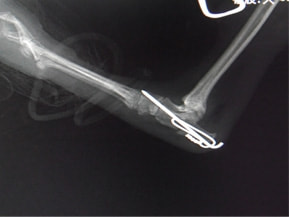

症例:交通事故による椎体脱臼

柴犬:9歳、避妊雌

交通事故直後、胸腰部に激しい疼痛、両後肢に完全麻痺を認め、シェフシェリントン徴候を呈していました。レントゲン検査において、第11-12胸椎間の脱臼が認められました。

脊髄の減圧、脊柱管の再構築・安定化を目的に、片側椎弓切除術およびMatrixMANDIBLE Plateによる椎体固定を実施しました。

隣接椎体を架橋するようにプレートを設置しました。

術後レントゲン写真